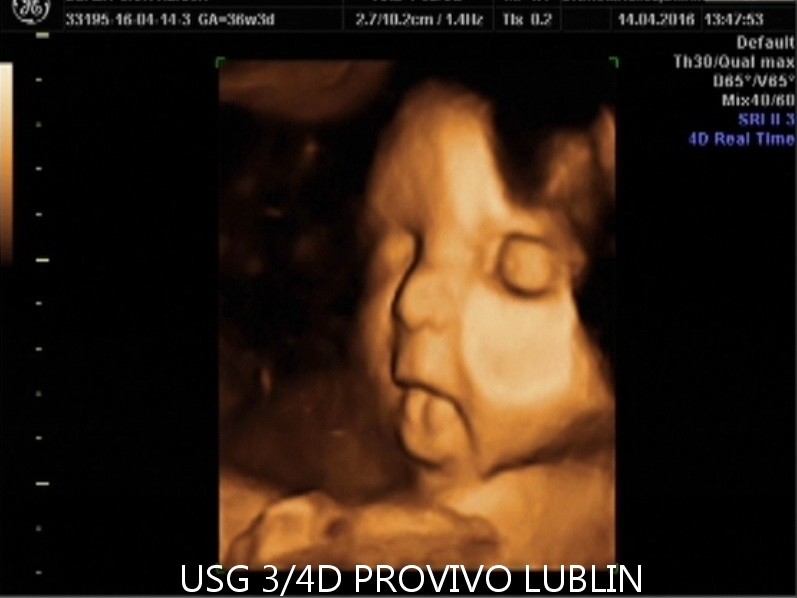

USG 3D daje możliwość trójwymiarowej rekonstrukcji obrazu płodu oraz wnętrza macicy. Dzięki temu można zobaczyć powierzchnię zewnętrzną ciała dziecka, a twarz płodu staje się znacznie wyraźniejsza niż w klasycznym badaniu 2D. To badanie szczególnie cenione przez rodziców, którzy chcą zobaczyć dziecko jeszcze przed porodem w bardziej realistyczny sposób. Na obecnej stronie PROVIVO wskazano również, że rodzice otrzymują zapis badania w formie elektronicznej.

USG 4D Lublin – obraz dziecka w czasie rzeczywistym

USG 4D pokazuje obraz podobny do badania 3D, ale dodatkowo rejestruje go w czasie rzeczywistym. Oznacza to, że rodzice mogą obserwować ruchy dziecka, mimikę twarzy i zachowanie płodu niemal jak podczas podglądu na żywo.